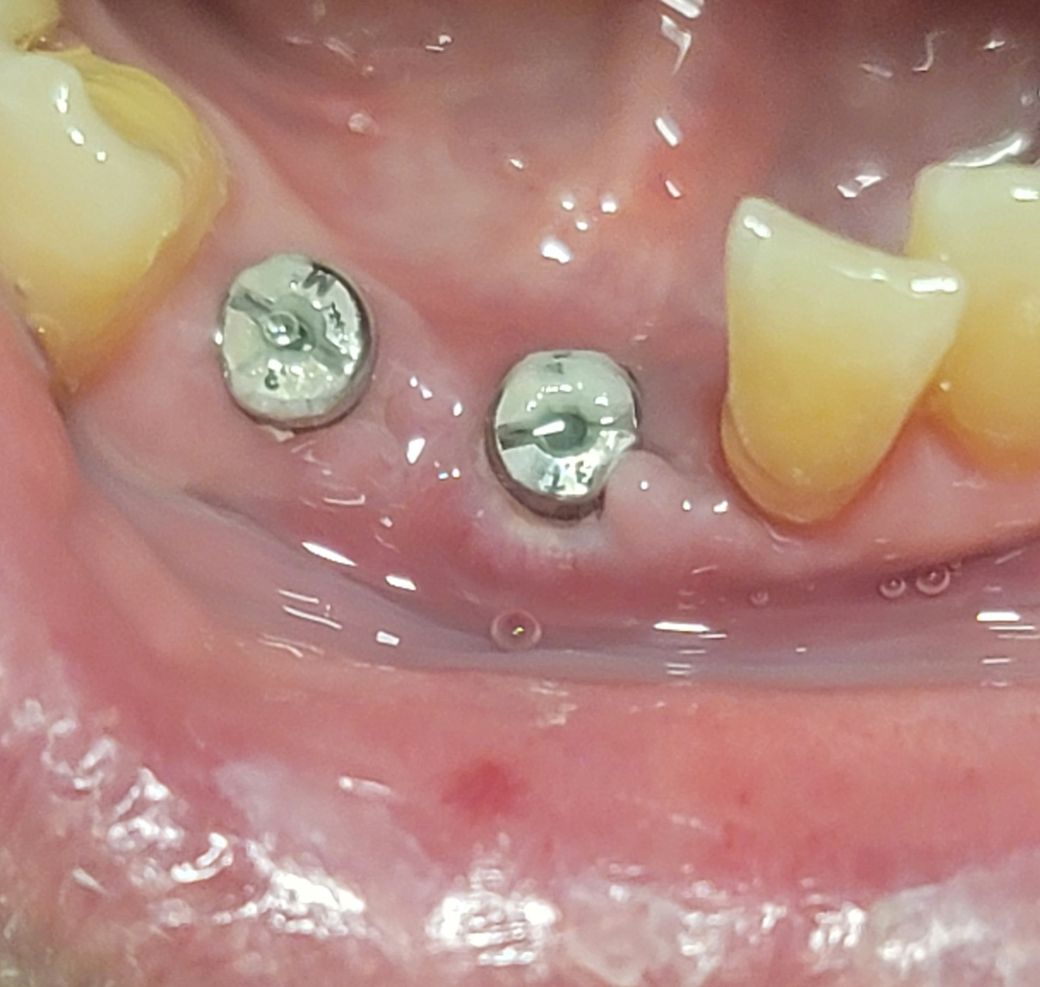

1) 현재 수술 후, 만 16일이 지난 상태인데, 힐링 어버트먼트가 육안으로 많이 보입니다. 수술 직후에는 힐링 어버트먼트가 거의 보이지 않았는데, 지금은 힐링 어버트먼트가 너무 노출되어 잇몸뼈 침식이 일어나는건가 걱정이 됩니다. 한마디로, 힘들게 인공 잇몸뼈로 잇몸뼈 성형을 했는데, 모조리 녹아내린건가 걱정이 됩니다. 아니면, 수술 후, 부어있는 잇몸에 붓기가 빠지면서 자연스럽게 노출된걸로 봐야 하나요? 치과에 빨리 예약하고 내원해서 상태를 점검 받아야 할까요?

4) 우측의 경우에 안쪽에 힐링어버트먼트를 감싸는 잇몸도 부족해보이고, 임플란트가 비쳐보이는 것 같습니다. 너무 좁은 앞니에 무리하게 임플란트를 한건 아닌지 걱정이 됩니다. 앞니 임플란트 부작용이라며, 잇몸뼈가 녹아서, 임플란트가 노출된 사진들이 많던데 덜컥 겁이 납니다. 어떻게 보시나요?

• 4번 째 사진

• 5번 째 사진

아래 앞니 경우에는 잇몸 뼈에 두께가 얇기 때문에 수술을 하고 난 다음에 임플란트 뿌리가 부분적으로 비춰 보일 수 있습니다.

골 유착만 잘 된다면 크게 문제가 되는 사항은 아니며 이후에 커스텀 지대주를 이용해서 제작을 한다면 자연스러운 치아를 만들 수 있을 것이라 생각됩니다. 자세한 확인을 위해서 치과에서 진료를 받아보세요.